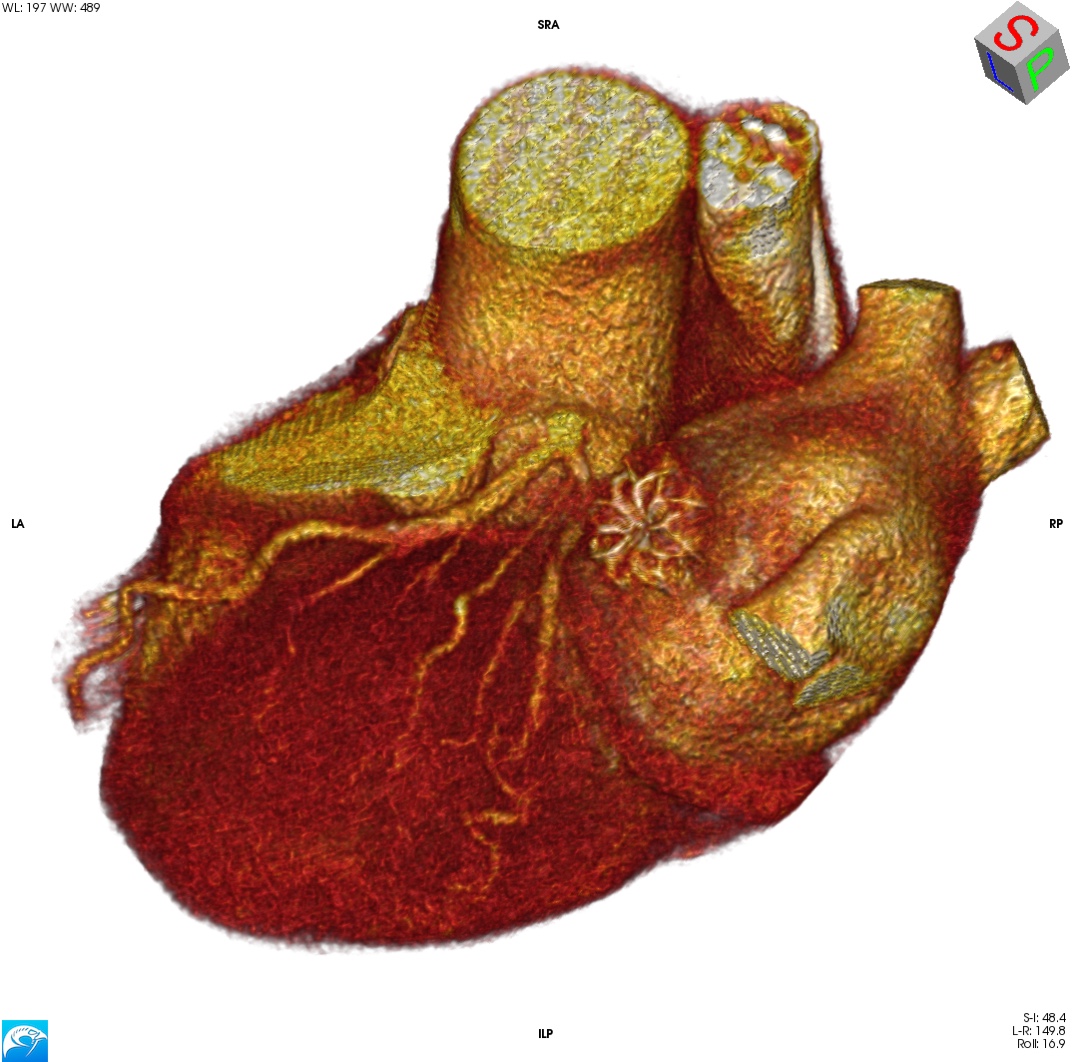

Όταν, λοιπόν, αποφασίζουμε να προχωρήσουμε, το αποτέλεσμα πρέπει να είναι κάπως έτσι:

Και στις MPR τομές, να μη φαίνεται σκιαγράφηση του σώματος του ωτίου — ακόμα και ένα μικρό peri-device leak (PDL) θα τo «ασπρίσει» –, ούτε βέβαια θρόμβος (device-related thrombosis, DRT).

Για σύγκριση, οι εικόνες CTA\ECG πριν την τοποθέτηση της συσκευής: